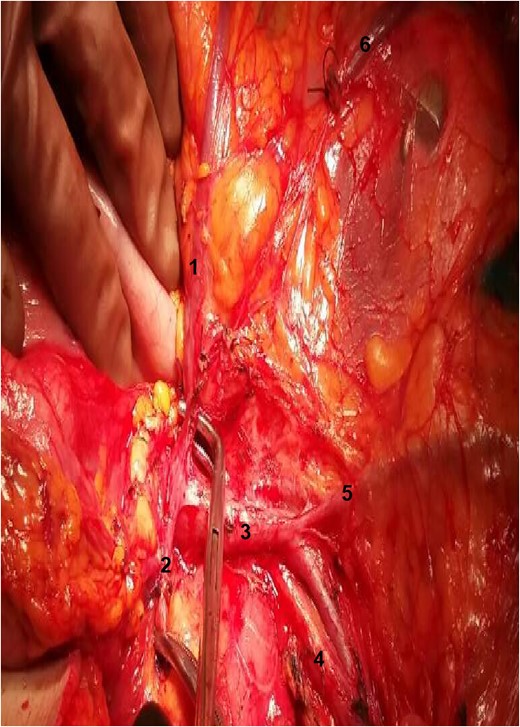

During the operation, surgeons attained to isolate the main supplying arteries of the right colon and their origins. The ileocolic and the middle colic arteries were observed, as typically, emerging as isolated vessels from the superior mesenteric artery (SMA). However, the origin of the RCA was nor observed from the SMA, nor from the previous arterial branches, as in common. Surgeons continued ascending dissection in order to detect the origin of the RCA that was finally observed arising from the right gastroepiploic artery (Figs 1–2). Pericolic lymph nodes and the lymph nodes that followed the central wards of the ileocolic, the middle colic and the aberrant RCA were gently dissected. The operation continued in the usual pattern. A drainage was placed and was finally removed the 6th postoperative day. The patient was discharged the 10th postoperative day with instructions. At the follow-up, the 14th postoperative day, the patient suffered no complications whatsoever.

The relation between the vessels: 1: gastroepiploic artery; 2: RCA; 3: superior mesenteric vein; 4: SMA.